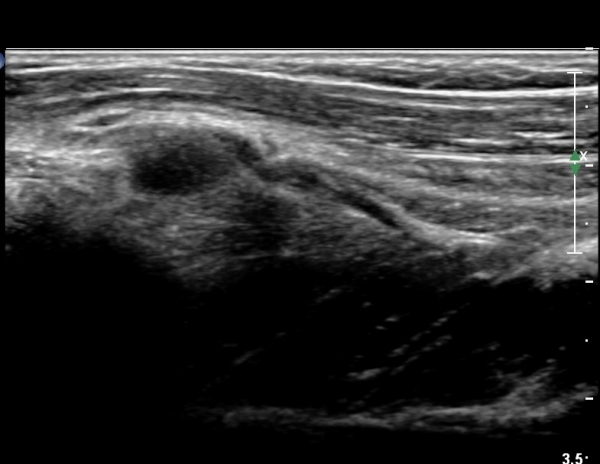

¿ä°ñµÎ ºÎÀ§ ÆÈ²ÞÄ¡ ¾Õ, ¿ÜÃø Ⱦ´Ü¸é°Ë»ç¿¡¼­ Èİñ°£ ½Å°æ ³»Ãø, ¿ä°ñµÎ Ç¥Ãþ¿¡¼­

ÀÛÀº ³¶Á¾ÀÌ °üÂûµÈ´Ù(»çÁø 3)

ŽÃÊÀÚ¸¦¸»´ÜÀ¸·Î  À̵¿ÇÏ´Ï ¿ä°ñ¸ñ ºÎÀ§¿¡¼­ Ä¿´Ù¶õ ³¶Á¾ÀÌ Èİñ°£ ½Å°æÀ» ¾Ð¹ÚÇÏ´Â °ÍÀÌ

°üÂûµÈ´Ù(»çÁø 4, 5)